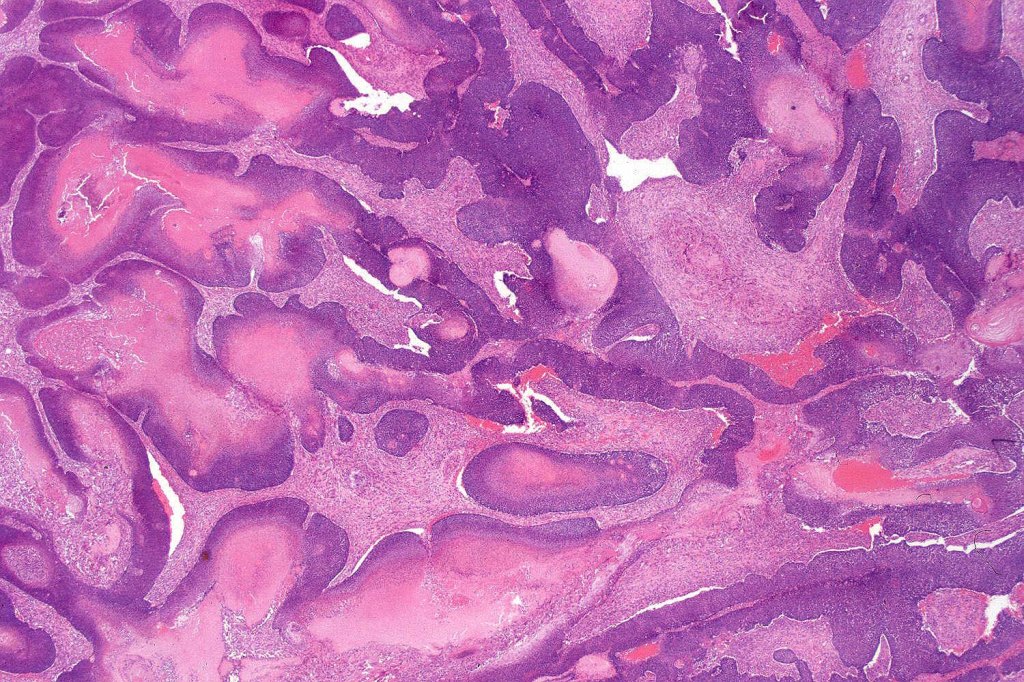

•Multilobulated tumor in dermis +/- subcutaneous fat with a fibrous pseudocapsule

•Basophilic small cells which transition towards supramatricial (orange staining) and ultimately ghost cells with intensely eosinophilic cytoplasm

•Foreign body reaction